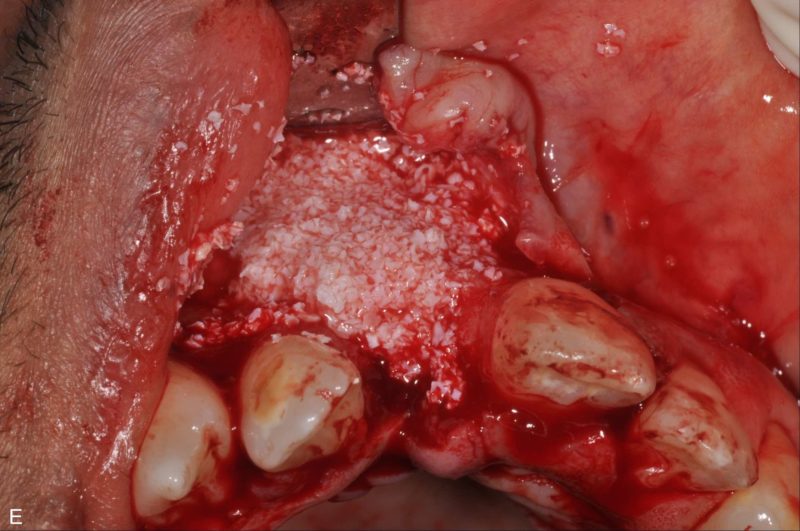

Regenerative material covered by collagene T-barrier membrane have been adapted to the vestibular side of the site. To maintain the volumes and make sure the material stays in place a T-barrer titanium membrane has been fixed on the implant, the flaps have been sutured to wait for healing. After 4 months we performed a new surgery to remove the membrane and insert a transmucosal healing screw.